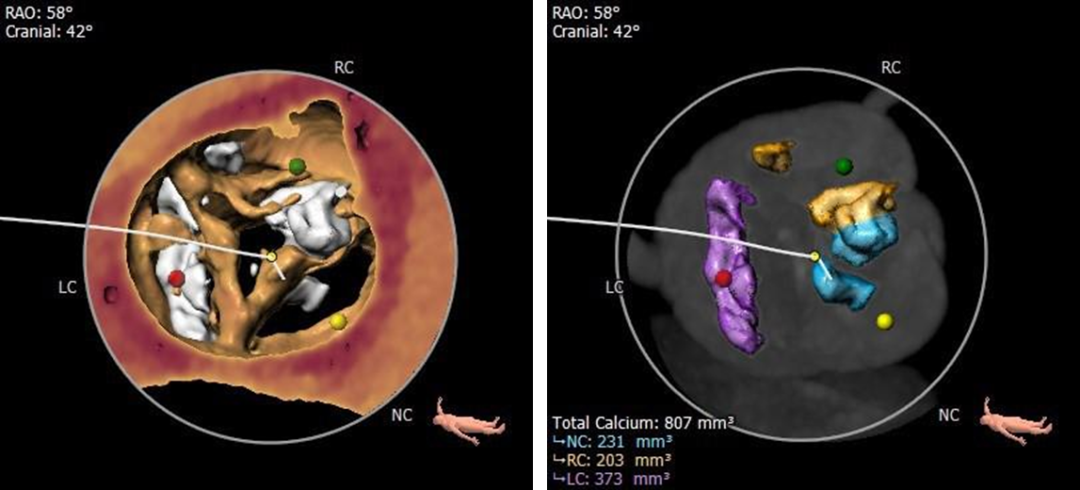

钙化分布:

重度钙化,HU850 807mm³。